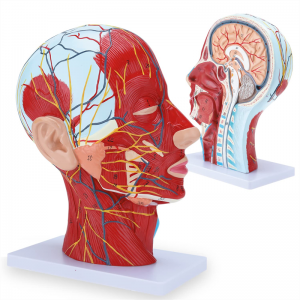

| Ciri -ciri | Model ini menunjukkan morfologi tempatan bahagian dalam dan luar bahagian median sagittal kepala dan leher, serta struktur saluran darah dan saraf, dan terdapat 84 bahagian yang menunjukkan tanda -tanda secara keseluruhan. |

【1: 1 LifeSize】 Seksyen Median 1: 1 Model otot vaskular neural yang besar dan leher besar (sebelah kanan). Pengerjaan yang baik. Menawarkan pelbagai ciri anatomi.

【Model otot neurovaskular cetek】 Sangat terperinci, nombor yang ditandai, telinga boleh dilepaskan, memperdalam pemahaman otot, kapal, saraf dan struktur dalaman kepala & leher. Red-artery, biru-vein, kuning-saraf.

【Ciri -ciri】 Ia menunjukkan otot -otot cetek muka yang terdedah; saluran darah cetek & saraf muka & kulit kepala; struktur dalaman kelenjar parotid & saluran pernafasan atas; Struktur keratan rentas sagittal tulang belakang serviks.

Model ini menunjukkan butiran leher kepala kanan dan bahagian pertengahan sagittal manusia. termasuk cetek

otot muka yang terdedah; saluran darah dangkal dan saraf muka dan kulit kepala; struktur dalaman

kelenjar parotid dan saluran pernafasan atas; Struktur keratan rentas sagittal tulang belakang serviks.

Model ini menunjukkan morfologi tempatan bahagian sagittal medial dan lateral kepala dan leher dan struktur vaskular dan sarafnya, dengan jumlah 100 petunjuk tapak.

Model ini adalah model otot neurovaskular yang besar dan leher yang besar, 1 komponen, menunjukkan butiran kepala kanan dan leher manusia dan bahagian sagittal median, termasuk otot -otot dangkal yang terdedah pada muka, kapal cetek muka dan skalp, saraf, saraf, saraf, saraf, saraf, saraf, saraf, saraf, saraf, saraf, saraf, saraf, saraf, saraf, saraf, saraf, saraf, saraf, saraf, saraf, saraf, saraf, saraf, saraf, saraf, saraf, saraf, saraf, saraf, saraf, saraf, saraf, saraf, saraf, saraf, dan struktur medial kelenjar parotid dan saluran pernafasan atas, dan struktur bahagian sagittal tulang belakang serviks